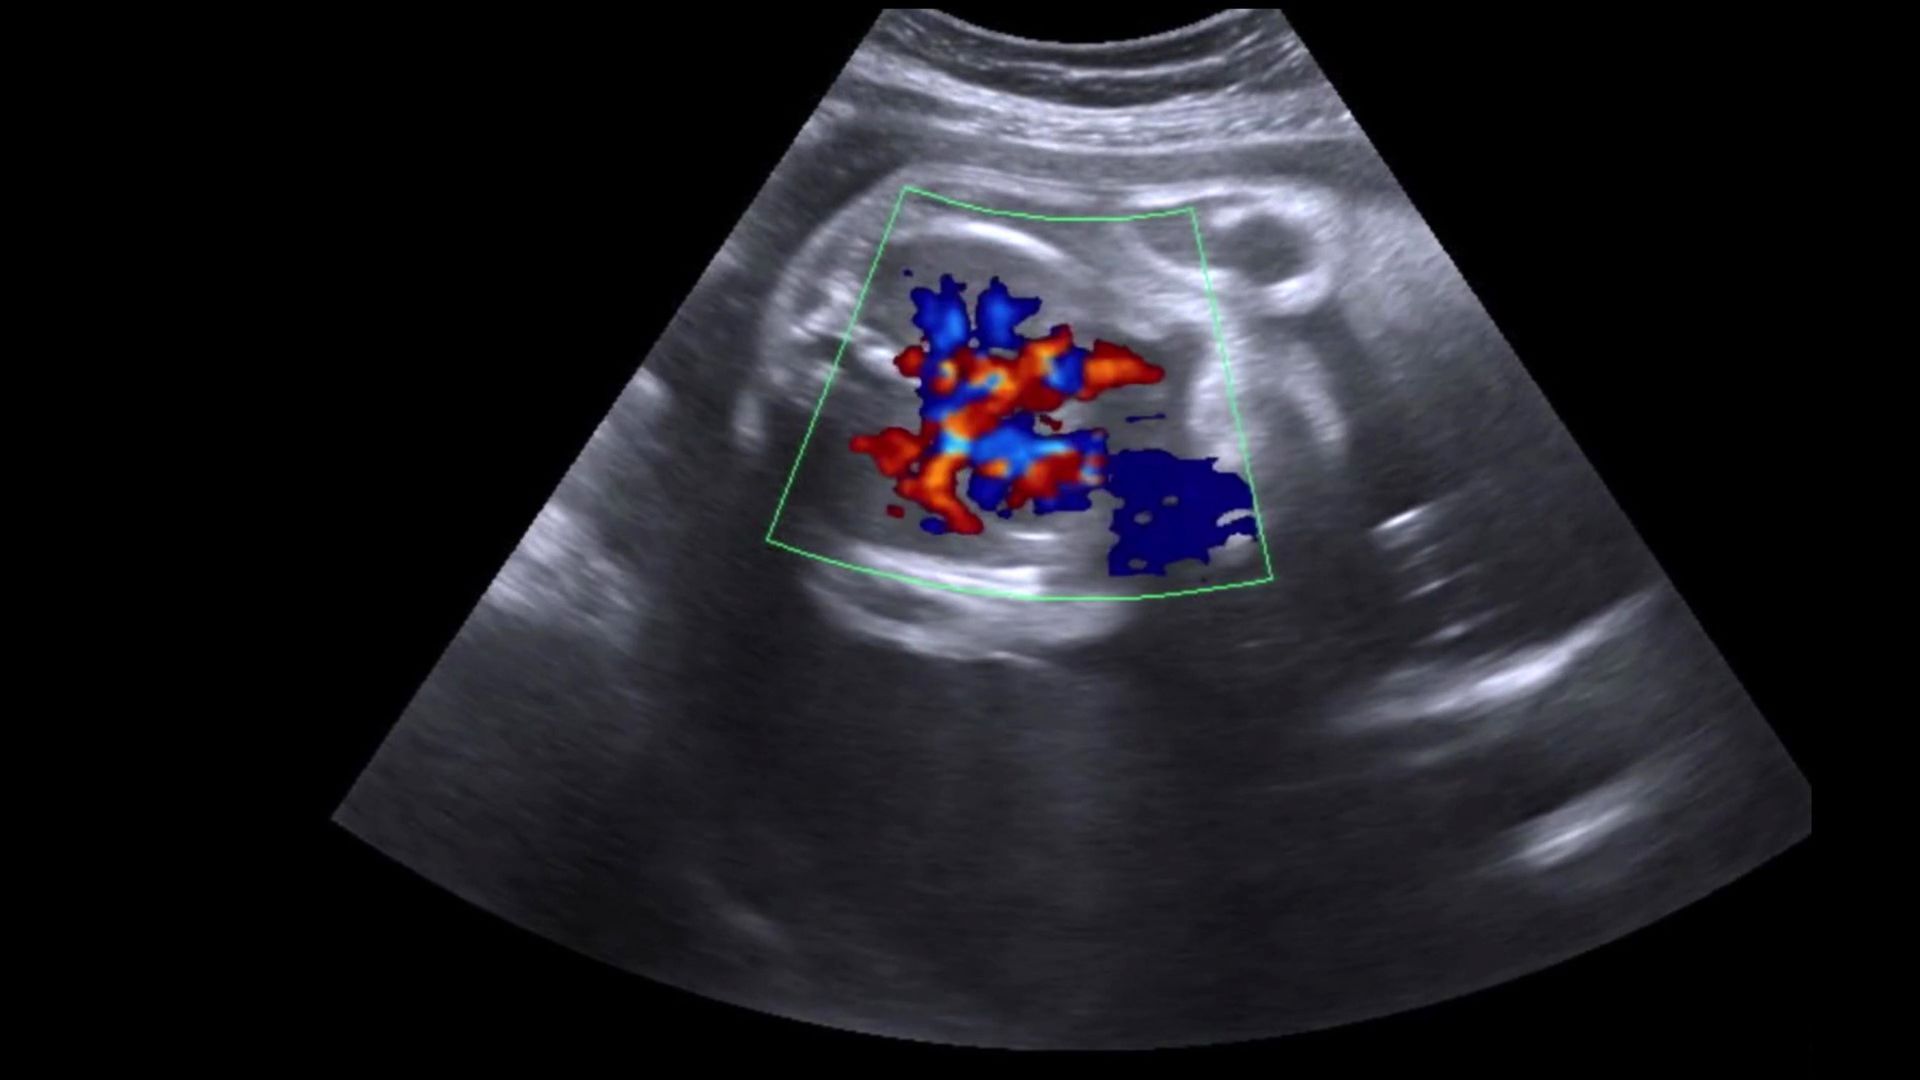

L'ecodoppler a Bari è un esame rapido e non invasivo che consente di rilevare anomalie o malattie mediante l’uso di onde sonore. Questo tipo di indagine rappresenta un'importante risorsa diagnostica, poiché permette di visualizzare in tempo reale la circolazione del sangue all'interno dei vasi, offrendo così informazioni preziose sulla salute cardiovascolare del paziente.

L'ecodoppler a Bari è una procedura diagnostica importante che viene eseguita in diverse sedi del corpo. Questa tecnologia avanzata consente di valutare la circolazione del sangue e di analizzare le condizioni dei vasi sanguigni. In particolare, tra le principali applicazioni dell’ecocolor doppler a Bari troviamo:

- l’ecodoppler cardiaco, una valutazione essenziale per analizzare la funzionalità del cuore e le condizioni delle sue valvole, determinando eventuali anomalie o malattie cardiovascolari.

L'ecodoppler a Bari viene eseguito utilizzando un'apparecchiatura ecografica avanzata che emette onde sonore ad alta frequenza, rendendo possibile una visualizzazione dettagliata delle strutture interne del corpo. Durante l'esame, il medico posiziona una sonda sulla pelle nelle aree specifiche da analizzare, e grazie alle immagini generate in tempo reale si possono osservare in modo chiaro il flusso e la velocità del sangue attraverso i vasi sanguigni. Questo tipo di ecografia è particolarmente utile per identificare eventuali problemi circolatori, come trombosi o stenosi, e per monitorare la salute cardiovascolare del paziente. Inoltre, l’ecocolor doppler offre un metodo non invasivo e indolore, permettendo così una diagnosi tempestiva e accurata, fondamentale per la gestione e la prevenzione di patologie vascolari.